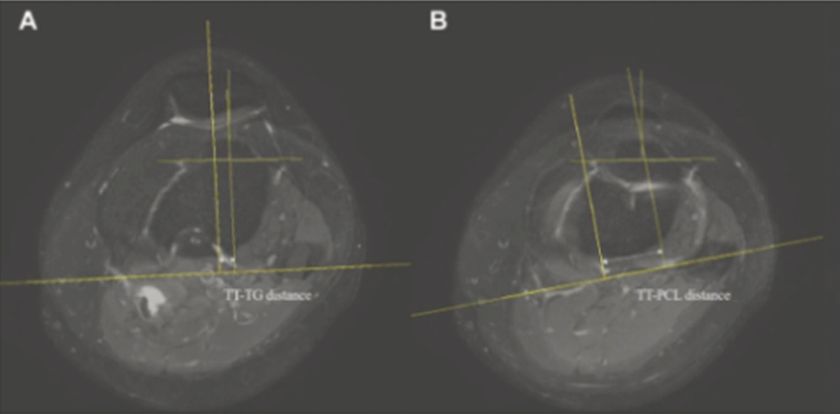

성인의 경우 경골결절과 활차구 사이(TT-TG) 및 경골결절과 후방십자인대 사이(TT-PCL) 거리로 불균형 여부를 판단하고, 슬개골을 제자리로 되돌리는 ‘원위부 재정렬 수술’을 시행한다.

이에 연구팀 분석결과 정상군에 속한 소아의 TT-TG 거리는 8.2mm, TT-PCL 거리는 19.5mm인 것으로 나타났다.

이는 불안정성군의 TT-TG 및 TT-PCL 거리인 16.1mm와 24.4mm와 비교해 유의하게 작은 수준이다.

특히 연구팀은 분석을 통해 소아청소년의 TT-TG 거리 14.9mm, 또는 TT-PCL 거리 23.7mm를 슬개골 불안정성 위험이 높아지는 기준 값으로 제시했다.